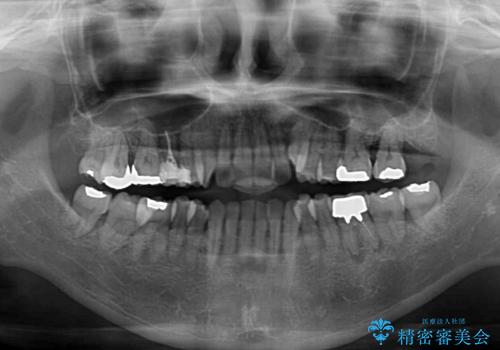

受け口傾向の骨格であり、前歯はクロスバイトまたは切端咬合となっており、下顎を中心に歯列全体の後方移動を行い、IPR(歯と歯の間を削る)によってデコボコが解消するように設計し、インビザラインにより治療を行うこととしました。

受け口傾向のインビザライン矯正は比較的治療を行いやすいため、きれいに仕上げることができました。舌の突出癖が顕著であったため、改善のためのトレーニングをしっかりと行っていただきました。